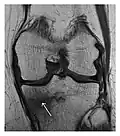

c

Figure 1: A 56-year-old woman presenting with left knee pain after a fall. (a) Initial anteroposterior radiograph was considered normal, however, subtle cortical disruption of the anterior rim of the medial tibial plateau, medial to the tibial spine, is noted (arrow). (b) Coronal T1-weighted MRI confirms the cortical disruption (arrow) and shows extensive fracture through the proximal tibia. (c) Coronal proton density-weighted image with fat saturation shows extensive edema in the subchondral bone. Note also hypersignal adjacent to the medial collateral ligament corresponding to a grade I sprain (arrowheads).[1]